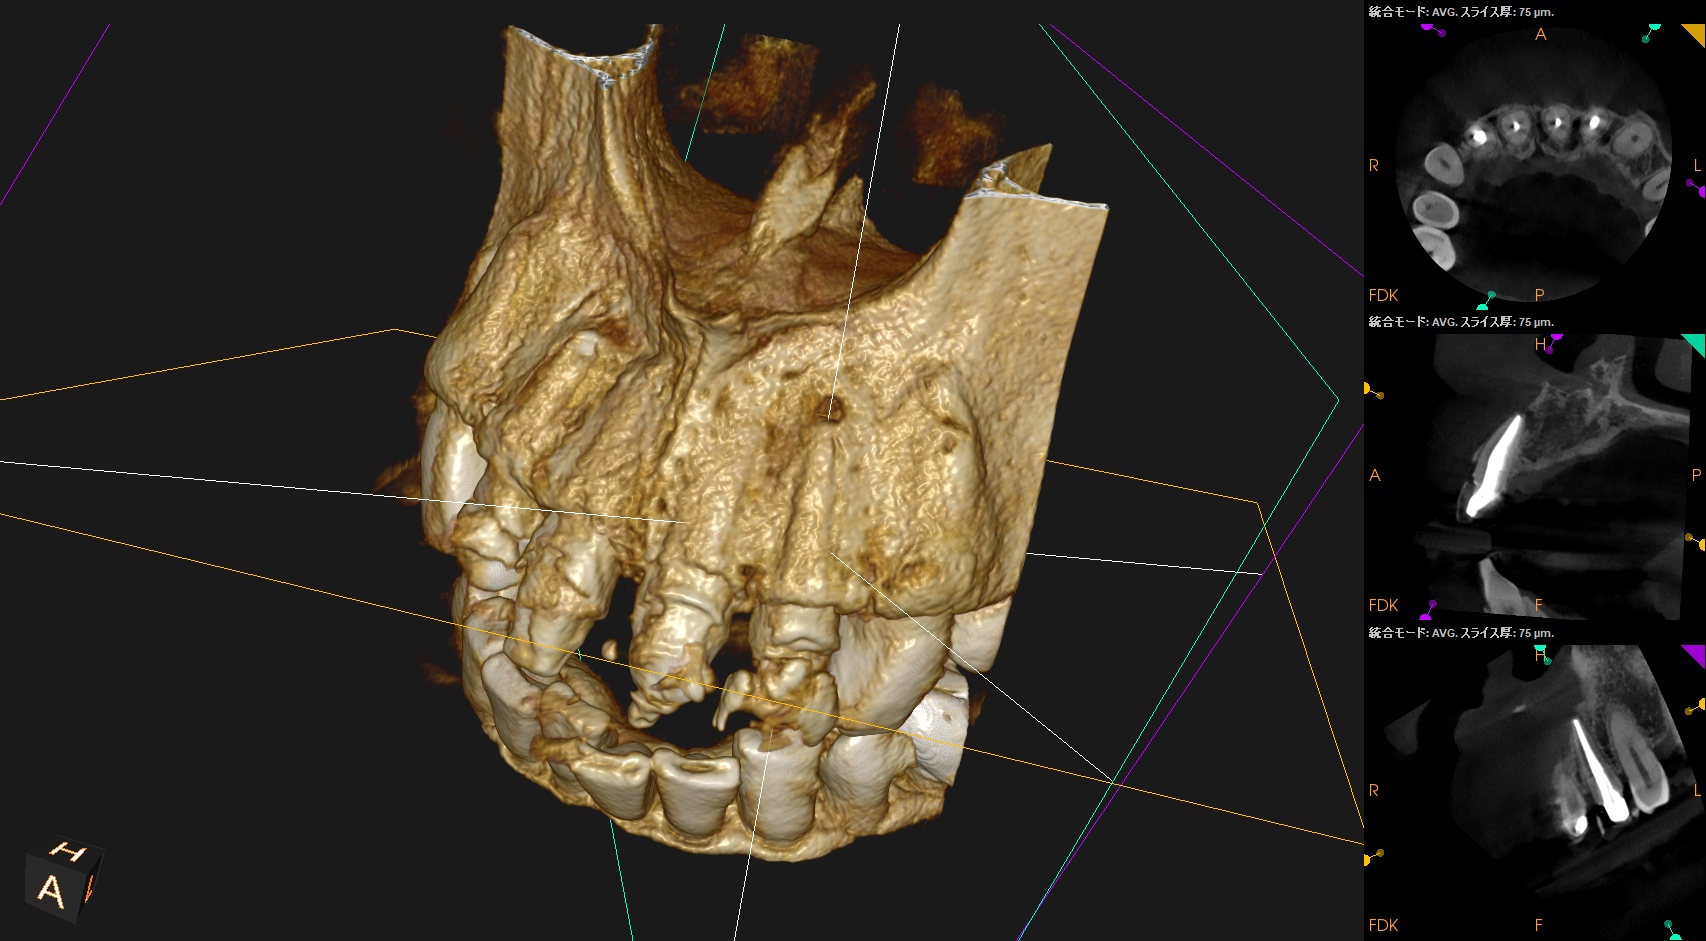

そこで、CBCTも撮影した。

#7

#10

これでも判然としかねる。

そこで、

CareStream(日本ではヨシダ社)のCBCTなら以下のようにMPR(Multi-Planar Reconstruction)画面を作成することができる。

それを過去のそれと比較してみた。

↓

このMPR画像からこの患者さんは#7,10ともに外科治療など要らないということがわかるだろう。

無論、検査の結果からそれは必要はないと言えるが、

客観的に不要であるということを患者さんに伝えるにもこの画像機能(MPR画像)は非常に有効である。

ということで今日は、このMPR画像機能について論じてみた。